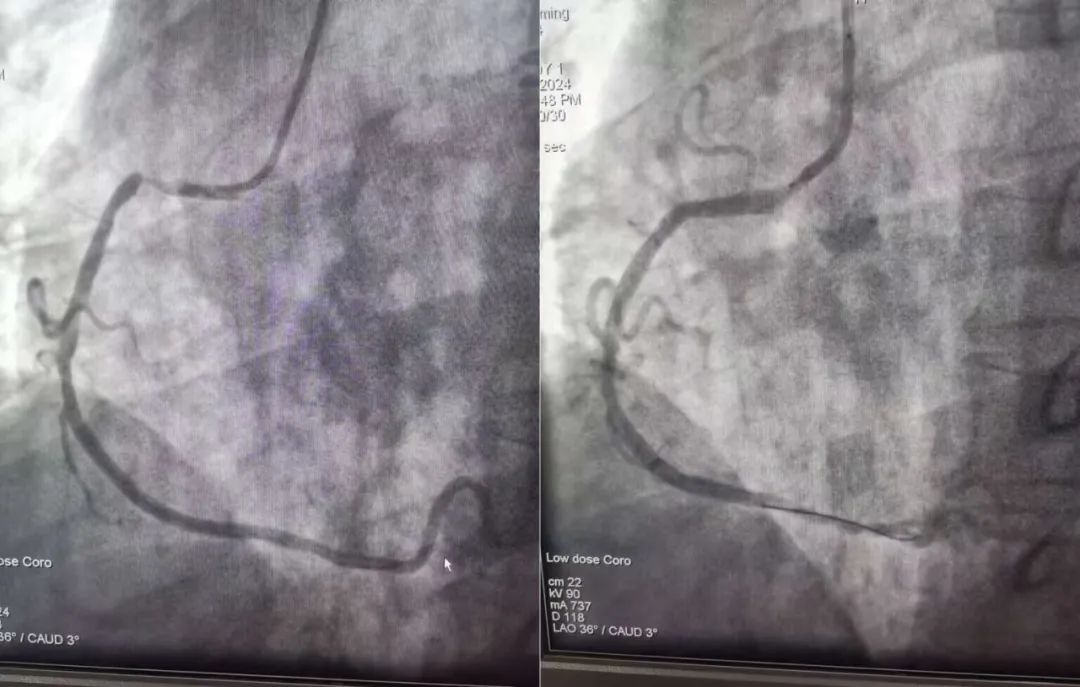

21:40楚雄州人民医院老师反馈:冠脉造影示:右冠次全闭塞,溶栓再通!手术过程:开通血管,病变部位植入支架,血流三级。